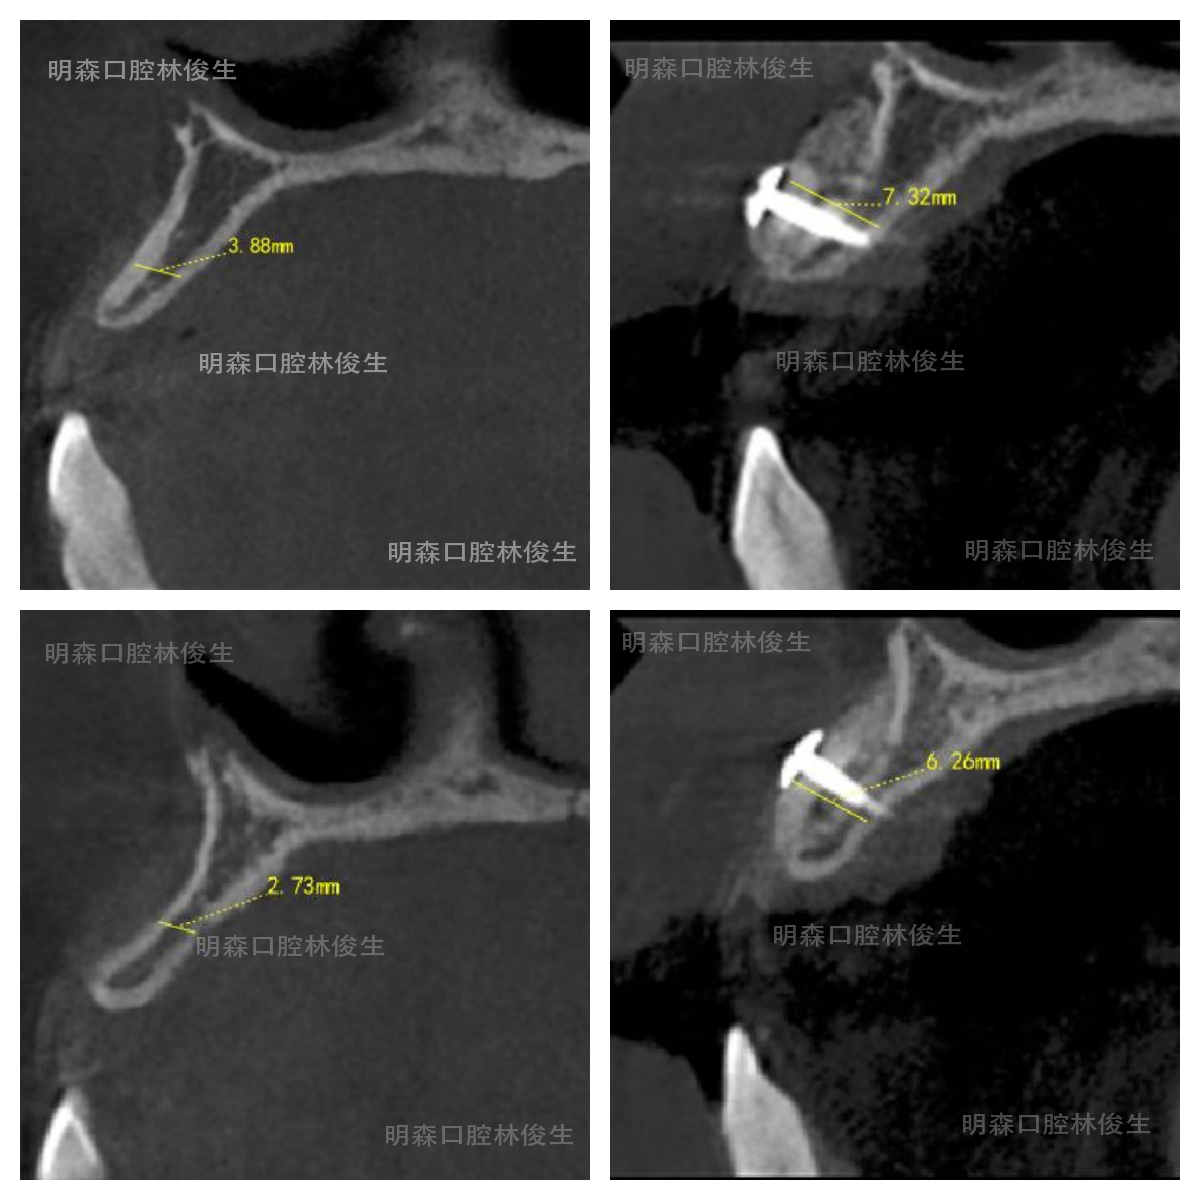

患者术前CT

因此,在第一期骨增量手术前我们先评估了,患者缺牙区在三维方向上软硬组织的缺损量及种植体植入的位置与轴向等,再根据骨缺损情况选择自体骨块移植术与小牛骨骨粉结合的骨增量手术方式实现修复。